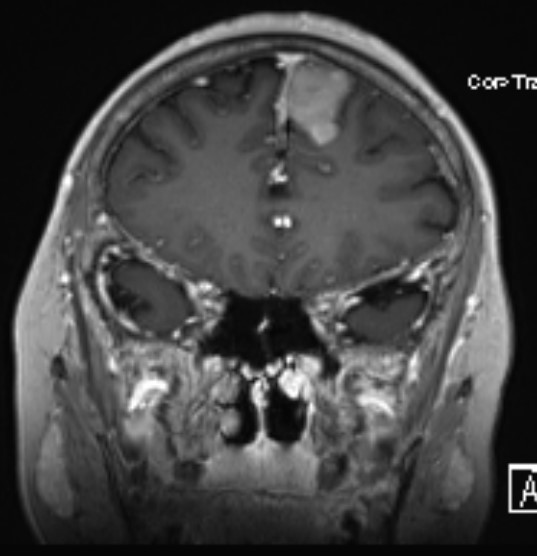

患者女性,62岁,因头晕一月在外院检查头部MR发现左额镰窦旁肿瘤来我院

完善术前检查在全麻下行左额开颅肿瘤切除术